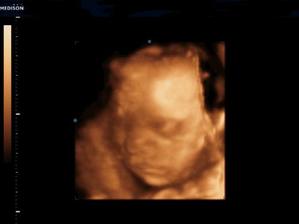

Naše kinderka

Dňa 24.8.2009 o 9.15 sa nám sekciou narodili naše krásne dvojičky Vanesska 2280 g a Larinka 2990 g. Robia nám veľkú radosť a moc ich ľúbime...